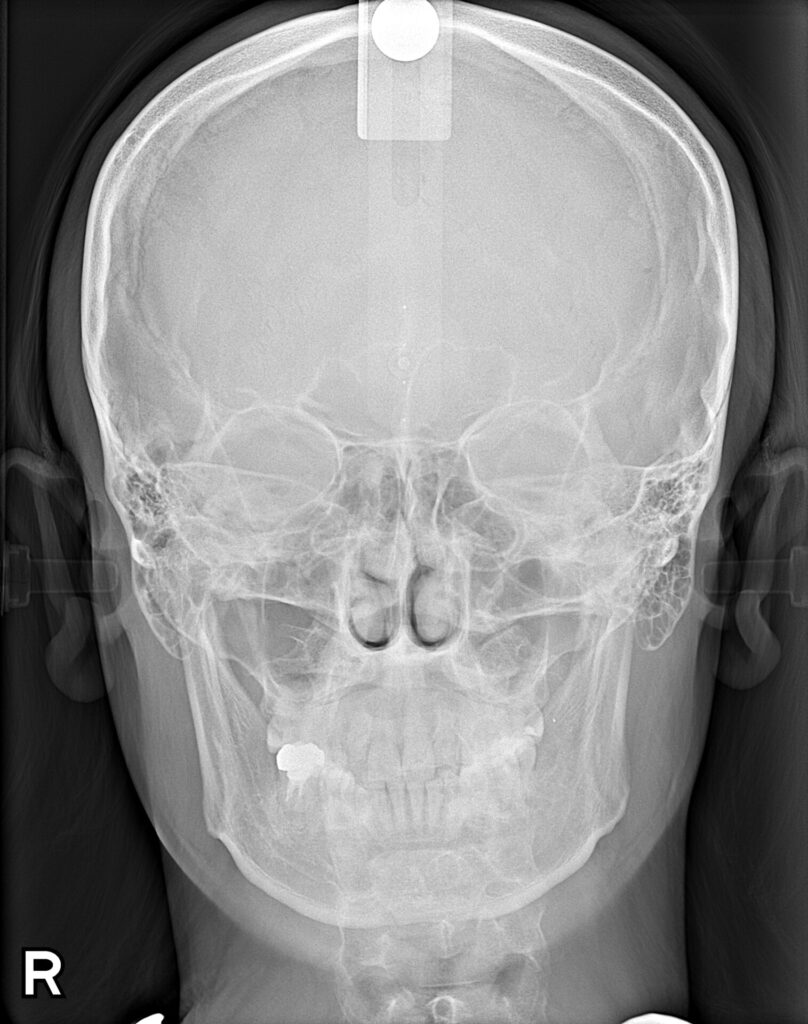

初回の無料カウンセリングで、「お口の中の写真」「横顔を含むお顔の写真」「レントゲン画像」などを撮影し、それらを元に、院長が一つひとつご説明します。

カウンセリングでは、お悩みやご希望など、どんな些細なことでもお伺いしております。検査では、口腔内検査の他にレントゲン撮影、3Dスキャン(歯の型取り)をします。